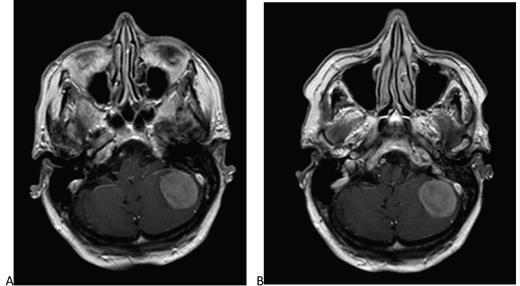

Leesburg, VA, June 17, 2021--According to ARRS' American Journal of Roentgenology (AJR) , a reduced dose of gadobutrol is non-inferior to 100%-standard dose of gadoterate for contrast-enhanced brain MRI.

In this international, prospective, multicenter, open-label, crossover trial (LEADER-75), 141 patients (78 men, 63 women; mean age, 58.5 years) with known or suspected CNS pathology underwent contrast-enhanced brain MRI with standard-dose gadoterate (0.1 mmol/ kg). If an enhancing lesion was identified, a second MRI with reduced-dose gadobutrol (0.075 mmol/kg) was performed within 15 days.

Comparison of reduced-dose gadobutrol and standard-dose gadoterate versus unenhanced imaging demonstrated noninferiority using 20% margin for three primary efficacy measures: subjective lesion enhancement, lesion border delineation, lesion internal morphology.

Furthermore, in post-hoc analysis, mean readings for subjective lesion enhancement, lesion border delineation, and lesion internal morphology differed by less than 1%--supporting equivalence using a narrow ±5% margin.